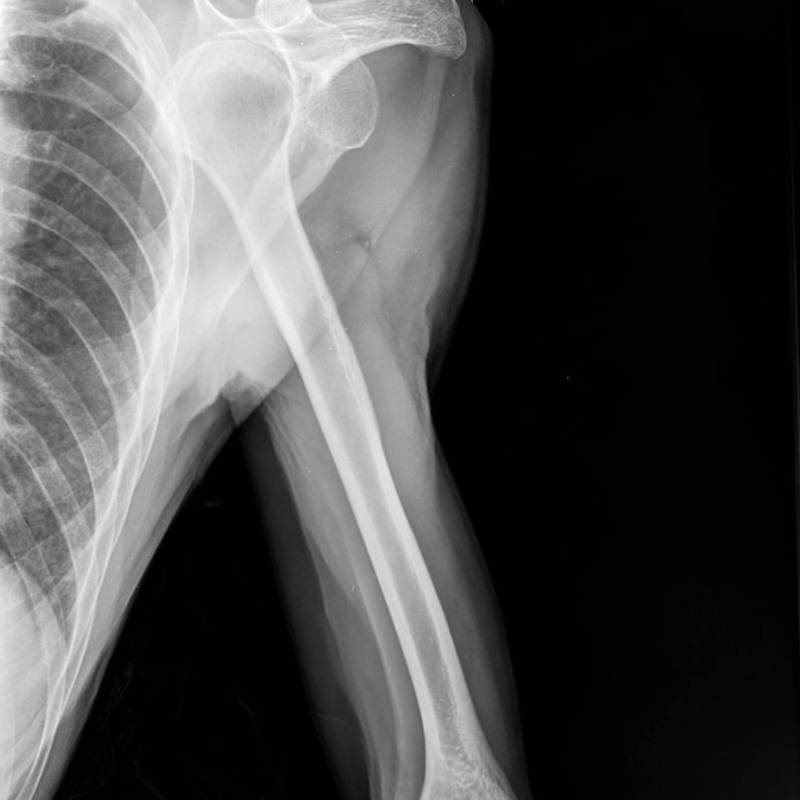

Digunakan untuk menilai tulang lengan bagi kecederaan atau kelainan.